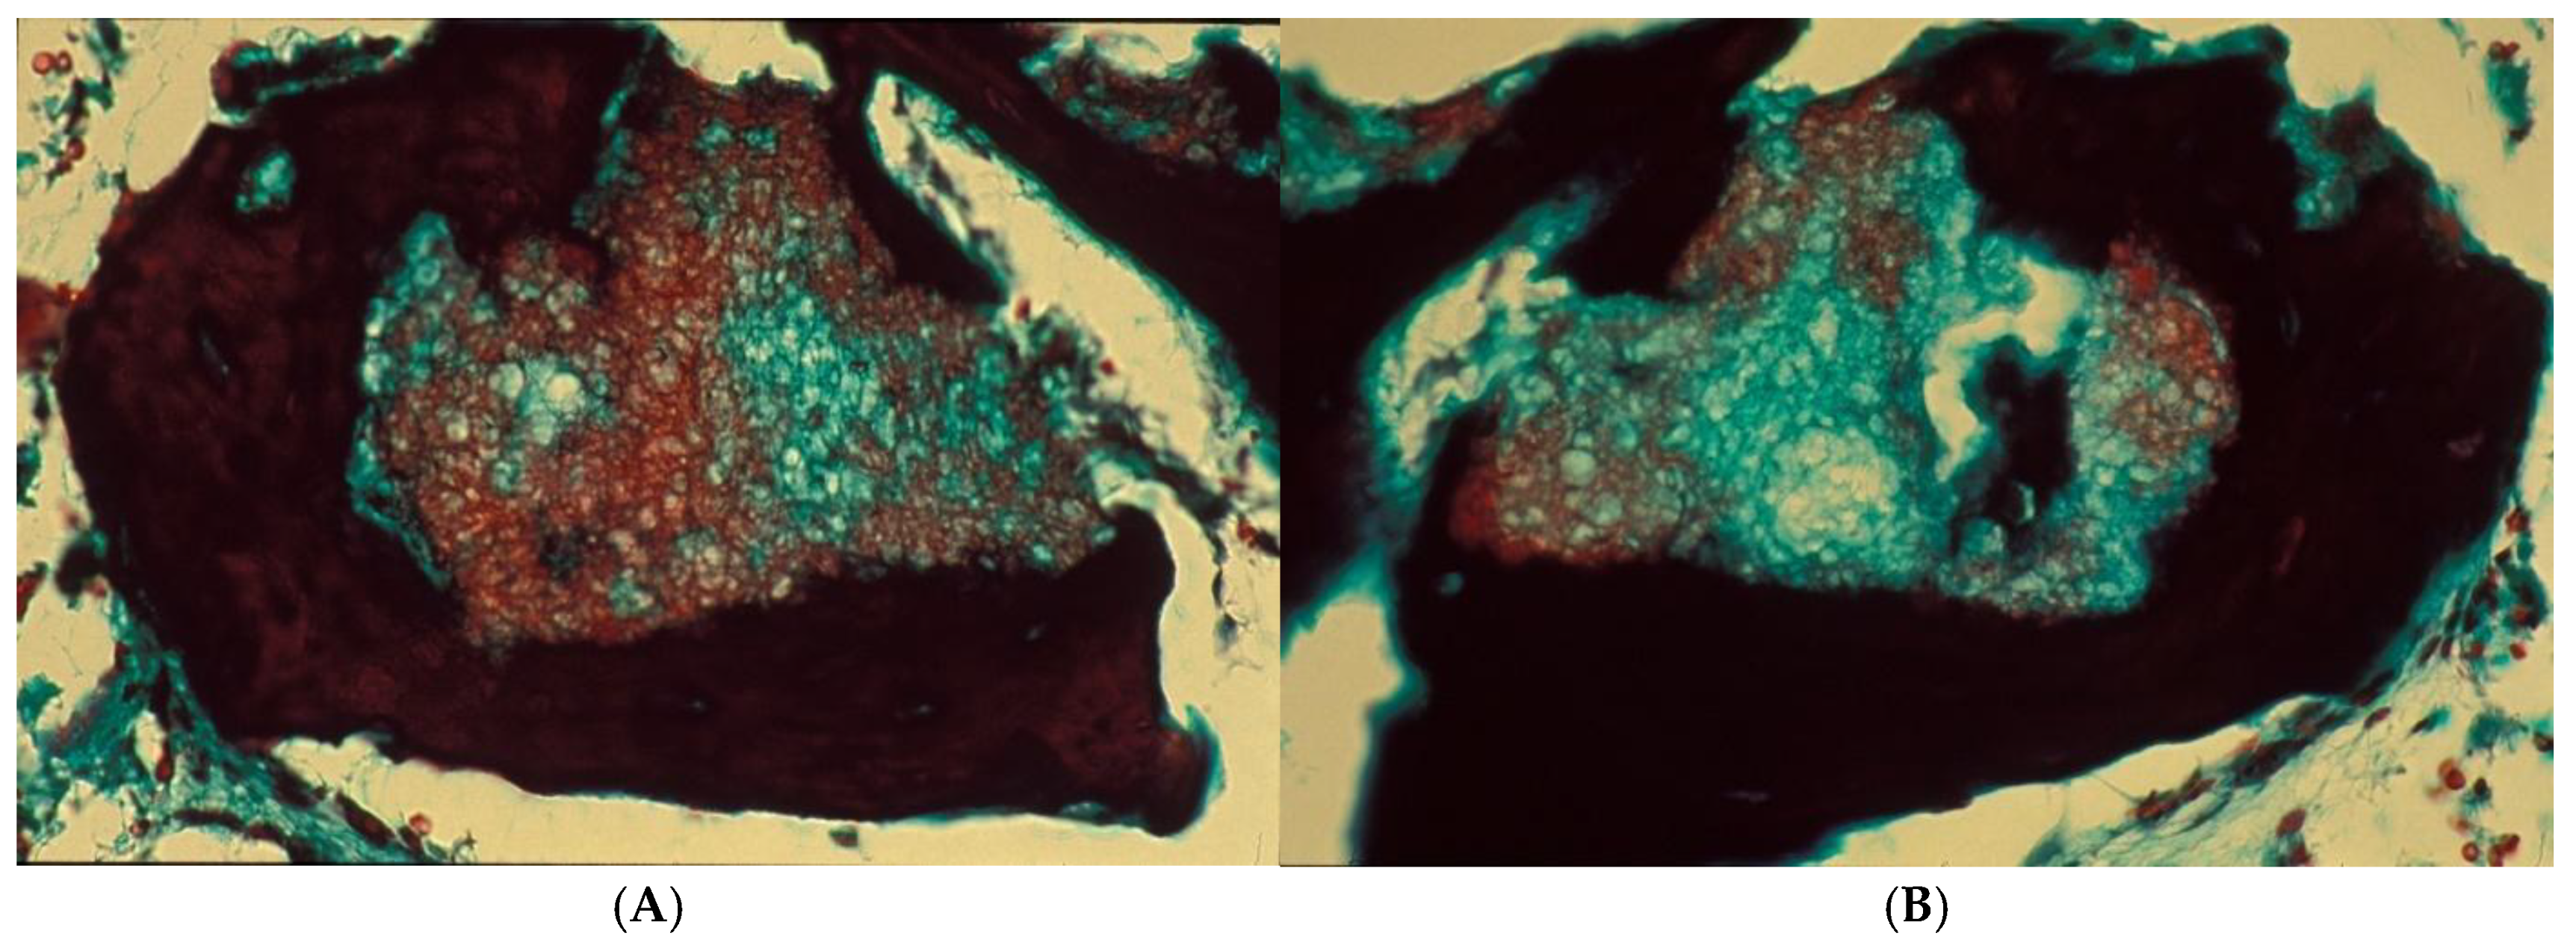

Figure 11.

NH remnants were found partially or entirely enclosed in appositionally formed new bone. Azan–Mallory staining, magnification 400× (A,B).

Histologic Evaluation

Light microscopic analysis (Figure 10A–D and Figure 11A,B) revealed new bone formation throughout all parts of the biopsy, with a homogeneous presence of trabecular bone structures in intimate contact with the surface of the NH granules, and marrow spaces filled with loose, highly vascularized connective tissue. There was no evidence of inflammation or a foreign body reaction around the NH remnants, which were found partially or completely enclosed in the appositionally formed new bone.

The bone structure consisted mostly of newly formed mature lamellar bone, with Haversian systems, cement lines, and osteocytes, highlighting the vitality of the bone tissue. The non-degraded NH granules appeared structurally porous and inhomogeneous, were partially surrounded by osteoid or woven bone, and were lined with seams of osteoblasts. Osteoid protrusion and extension into the graft material were observed. Fibrovascular extension with osteoid deposition within the nanostructured porous granule was observed, which was composed of cellular fibrous connective tissue undergoing mineralization, thereby creating an arboreal network.

The presence, around the same granule, of a side with osteoclasts, as well as an osteogenic side with osteoblasts, was observed, demonstrating the integration of the biomaterial.